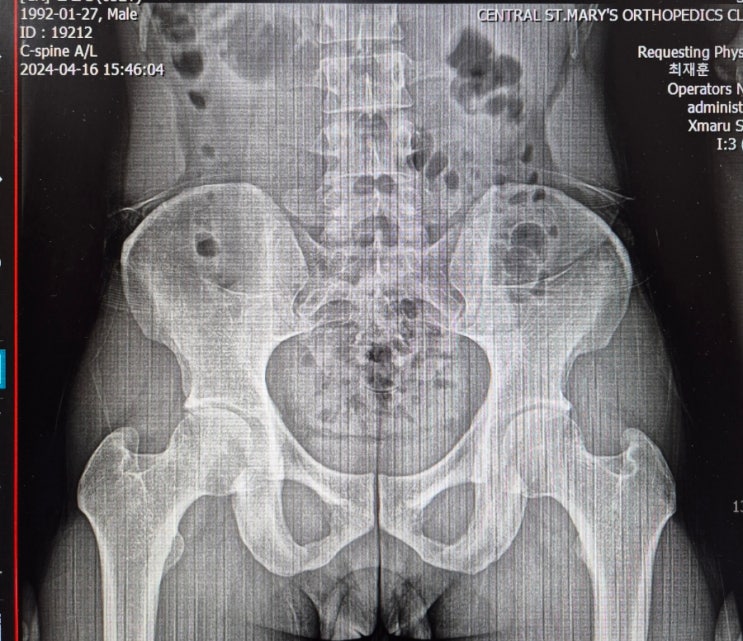

x-ray l 골반이 뒤집어져 있다.

뒤집어진 골반. x-ray 상 ilium 바깥면이 넓게 나온다. ( IN 과는 다른 개념 ) 골반이 서있는 게 아니라 ...